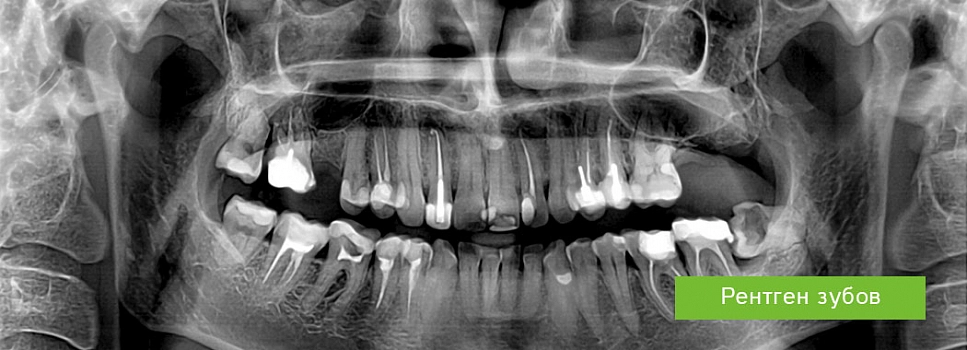

Рентгенография в выявлении скрытых очагов инфекции⁚ надежный метод диагностики

В современной медицине своевременная и точная диагностика играет ключевую роль в успешном лечении различных заболеваний. Особую сложность представляют скрытые очаги инфекции, которые могут долгое время протекать бессимптомно, постепенно разрушая ткани и органы. Рентгенография, несмотря на появление более современных методов визуализации, остается одним из наиболее доступных и информативных способов выявления таких очагов, особенно на ранних стадиях. В этой статье мы подробно рассмотрим возможности рентгенологического исследования в диагностике скрытых инфекций, его преимущества и ограничения, а также области применения.

Рентгенологическое исследование обладает рядом преимуществ, делающих его ценным инструментом в выявлении скрытых очагов инфекции. Во-первых, это высокая доступность и относительно низкая стоимость процедуры, что делает ее доступной для широкого круга пациентов. Во-вторых, рентгенография позволяет быстро получить изображение исследуемой области, что особенно важно в случае острых инфекционных заболеваний, требующих немедленного лечения. В-третьих, метод обладает хорошей разрешающей способностью, позволяющей визуализировать изменения в плотности тканей, характерные для многих инфекционных процессов.

Например, при пневмонии рентгенография может показать характерные очаги затемнения в легких, указывающие на воспаление. При остеомиелите (инфекционном поражении костей) рентгеновский снимок может выявить деструктивные изменения костной ткани, а при абсцессах – образование полостей, заполненных гноем. Однако, следует помнить, что на ранних стадиях инфекции рентгенологические изменения могут быть минимальными или вовсе отсутствовать.

Рентгенография эффективна для выявления различных инфекционных процессов, затрагивающих костную систему, легкие, мягкие ткани и другие органы. В таблице ниже приведены примеры заболеваний, диагностика которых может быть осуществлена с помощью рентгенографии⁚